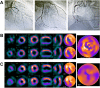

The aim of this study was to assess the washout rate (WOR) for thallium-201-chloride single-photon emission computed tomography (SPECT) myocardial perfusion imaging (MPI) using cadmium zinc telluride detectors for SPECT (CZT SPECT) versus conventional Anger-type SPECT (conventional SPECT). A total of 52 Japanese patients were examined using CZT SPECT and conventional SPECT, and the global WORs were compared. Additionally, the MPI WORs were compared for patients with a normal MPI versus those in whom MPI reflected the patients' multivessel disease (MVD) MPI. Washout rates were similar when approximated by CZT SPECT versus conventional SPECT 12.59 ± 2.26%/h vs 12.57 ± 2.27%/h ( P = .997), respectively. The WOR values for CZT SPECT versus conventional SPECT were 13.42%/h (1.53%/h) vs 13.93%/h (1.24%/h) ( P = .337), respectively, for 7 normal MPI patients, and 10.64 ± 2.20%/h vs 10.84 ± 2.26%/h ( P = .848), respectively, for 7 MVD-MPI patients. The WOR values for normal MPI versus MVD-MPI patients for CZT SPECT were 13.42 ± 1.53%/h vs 10.64 ± 2.20%/h ( P = .025), respectively. Thallium-201-chloride WOR values obtained with high-efficiency CZT SPECT, which enabled significantly reduced imaging times and use of a low-dose protocol, were similar to those obtained with conventional SPECT.